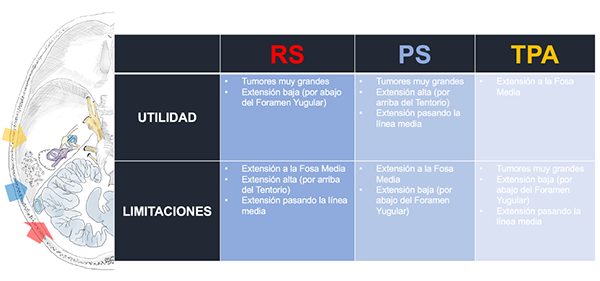

Actualmente, no existe un consenso en la elección de un abordaje quirúrgico ideal para acceder a la región petroclival; sin embargo, la extensión del tumor, la relación con el tentorio y el compromiso neurológico pueden inclinar la balanza hacia algún tipo de abordaje. Muchos cirujanos han propuesto herramientas para la elección de un abordaje específico, pero éstas pueden perder valor cuando se individualiza cada caso en particular. Recientemente Guinto et al. propusieron un sistema de medición que evalúa las bondades del abordaje retrosigmoideo en el manejo de los meningiomas petroclivales puros dependiente del grado de desplazamiento y posición del pedúnculo cerebeloso medio en relación al tumor. Los autores del presente trabajo consideran que el abordaje debe estar basado principalmente en la zona de implantación de tumor, que puede ser clival, petroclival o petrosa anterior, en la relación que existe entre la lesión y el tentorio, y en la extensión o no a la fosa media (Figura 12). Para las zonas clival y petroclival, el abordaje retrosigmoideo es preferido cuando el tumor se ubica por debajo del nivel del tentorio. En caso de una extensión tumoral alta, por arriba del tentorio, el abordaje presigmoideo es de mayor utilidad. Para los tumores con implantación en la zona petrosa anterior sin extensión a la fosa media una buena opción es el abordaje retrosigmoideo, en general utilizando el fresado del tubérculo suprameatal. Si existe extensión a la fosa media el abordaje indicado es el transpetroso anterior En algunas situaciones muy puntuales es necesario combinar abordajes para resolver de mejor manera el caso (Figura 13).

Figura 12. Tipos de Abordajes para MRPC. Presentamos los distintos tipos de abordajes típicamente utilizados para tratar los MRPC. Señalamos de cada abordaje sus bondades y limitaciones.